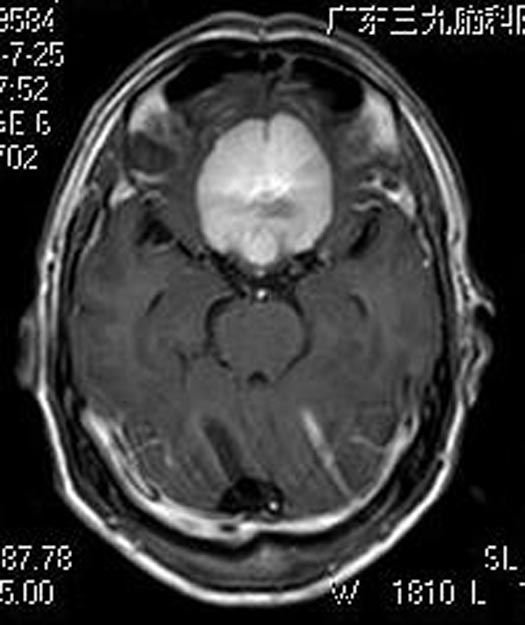

儿女们认为父亲视力下降肯定是有原因,在孩子们的劝说下,申先生来到广东三九脑科医院综合神经外科。头颅MR检查提示:前颅底占位病灶,考虑颅底脑膜瘤(大小约49.9mm×47.0mm×25.0mm),瘤灶后缘挤压视交叉。头颅CTA检查提示:前颅窝底占位性病变血管丰富,与双侧大脑前动脉A1、2段关系密切,考虑脑膜瘤。

鲁明主任告诉申先生:肿瘤继续压迫将会对视神经产生不可逆的损害。家属积极地要求手术治疗。由鲁明主任主刀,在全麻下行经右额前颅底巨大脑膜瘤切除术,术中见白色肿瘤,质韧,边界清,肿瘤与右视神经大脑前有粘连,视交叉及右视神经受肿瘤压迫,锐性分离肿瘤与神经、肿瘤与血管、以相同手术跨大脑镰分离左颅底肿瘤、肿瘤与左侧视神经,镜下全切肿瘤,解剖保留双侧视神经、神交叉,双侧大脑前动脉,手术顺利。术后申先生视力明显好转,病理结果提示:过渡型脑膜瘤 WHO I级。